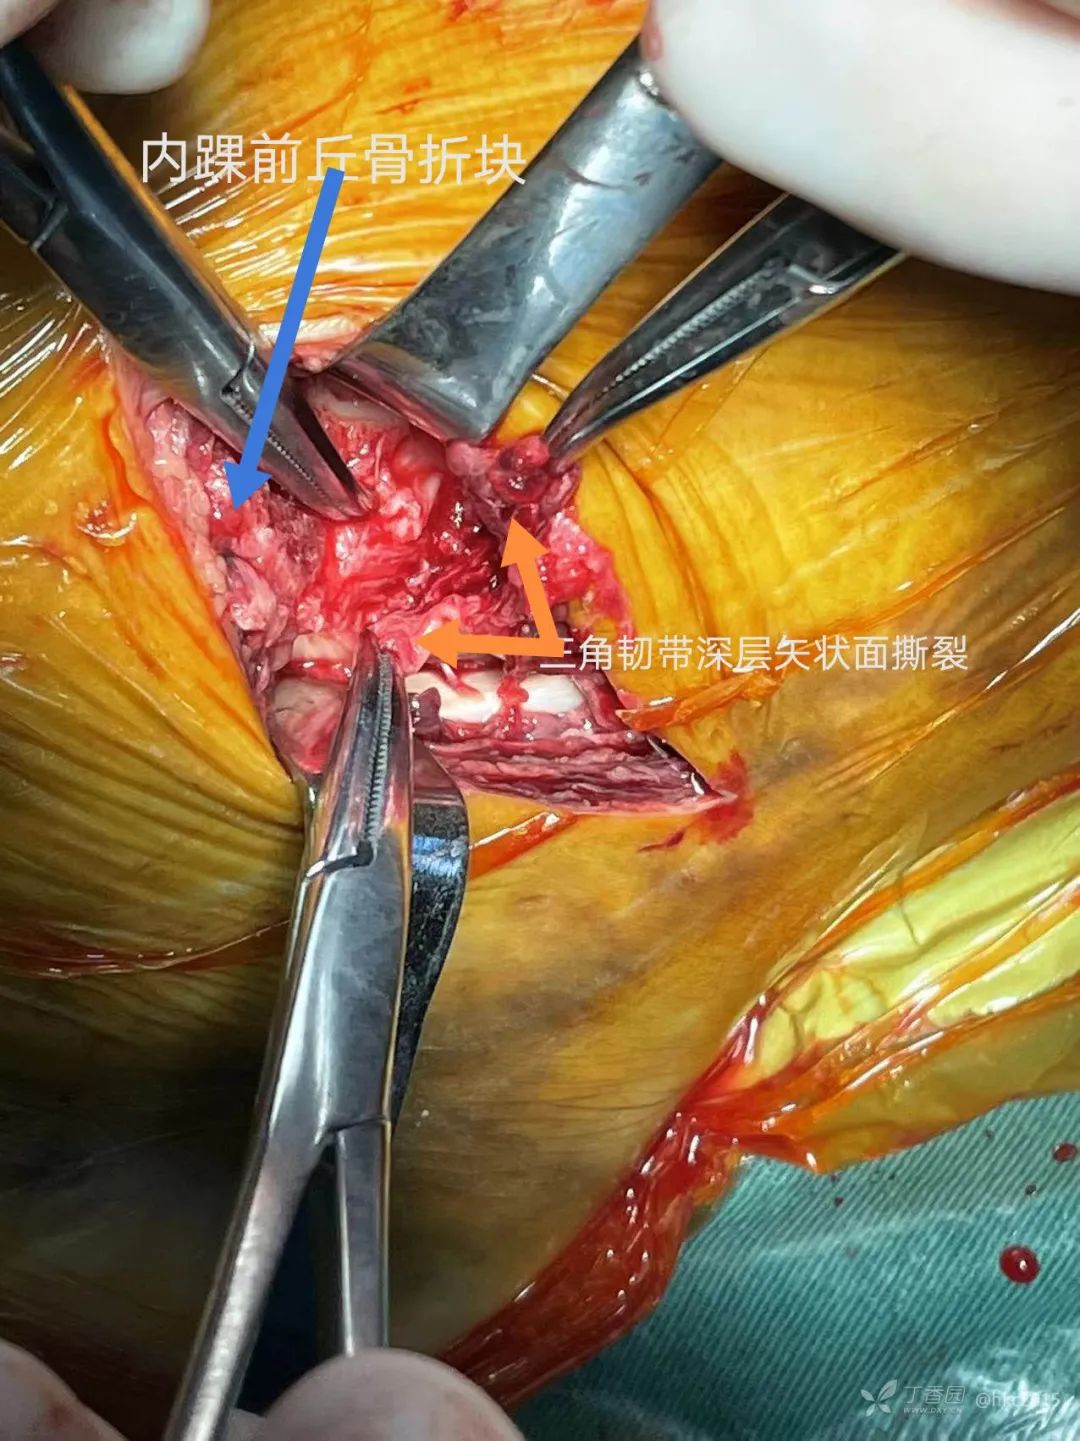

这是一例三踝骨折的患者。

术中发现三角韧带深层矢状面撕裂

术中将骨折与韧带损伤一一处理。